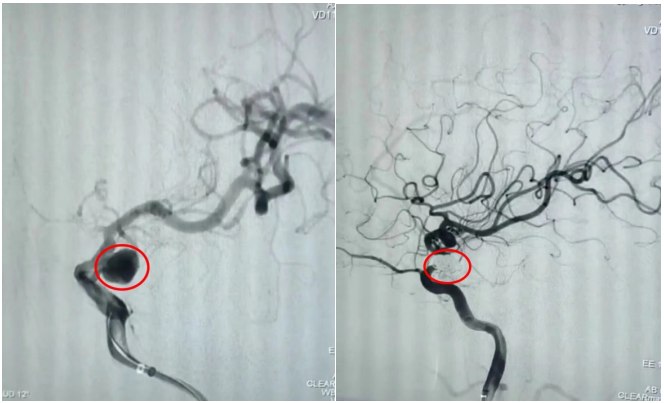

通訊員劉洋、劉立君報(bào)道: 9月2日家住衡山縣的劉爺爺從衡陽(yáng)市中心醫(yī)院神經(jīng)內(nèi)科出院了。劉爺爺8月22日因左側(cè)頸內(nèi)動(dòng)脈后交通段動(dòng)脈瘤破裂致蛛網(wǎng)膜下腔出血,病情危在旦夕,在衡山縣人民醫(yī)院行急診全腦血管造影明確病因后,連夜轉(zhuǎn)入衡陽(yáng)市中心醫(yī)院神經(jīng)內(nèi)科治療。衡陽(yáng)市中心醫(yī)院神經(jīng)內(nèi)科介入團(tuán)隊(duì)立即接手病人,經(jīng)過(guò)認(rèn)真查看病人、細(xì)致分析病情,聯(lián)合介入室、麻醉科為病人緊急行動(dòng)脈瘤介入栓塞術(shù),手術(shù)順利,術(shù)后通過(guò)腦脊液置換、預(yù)防腦動(dòng)脈痙攣、預(yù)防深靜脈血栓、預(yù)防感染等綜合治療措施,緩解了劉爺爺?shù)念^痛癥狀,避免了并發(fā)癥的發(fā)生,10天后劉爺爺又回到了衡山縣人民醫(yī)院進(jìn)行后續(xù)康復(fù)治療。